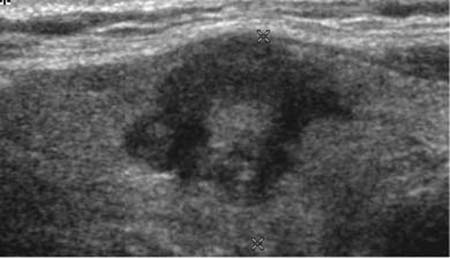

Ultraschall - echoarmer, unscharf begrenzter Knoten mit Krebsverdacht

Liegt ein kalter Knoten vor, so muss abgeklärt werden, ob es sich um einen "harmlosen" Knoten handelt oder ob Verdacht auf Schilddrüsenkrebs besteht. Neben der Szintigraphie ist heute primär der Ultraschall (Sonographie) die wichtigste Untersuchung zur Abklärung und Einschätzung von Knoten. "Echoreiche" und gut abgrenzbare Knoten deuten auf gutartigen Charakter hin harte, echoarme und schlecht abgrenzbare Adenome sind eher kritische Zeichen ebenso Knoten mit Mikrokalk, vor allem, wenn dasselbe Ultraschallmuster auch in Lymphknoten vorliegt. Metastasen in Lymphknoten zeigen häufig dasselbe Gewebebild.

Sono bösartiger Knoten mikrokalk lnn metastase